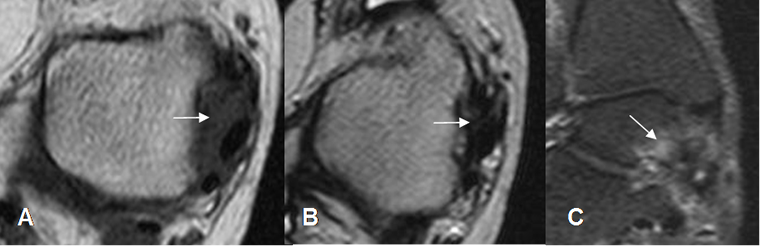

Fig 102. Pinzamiento posterolateral.

A: RM axial en T1, B: RM axial en T2 y C: RM coronal en STIR. Tejido inflamatorio hipointenso en T1 e hiperintenso en T2 y STIR, en la parte posterolateral del tobillo.